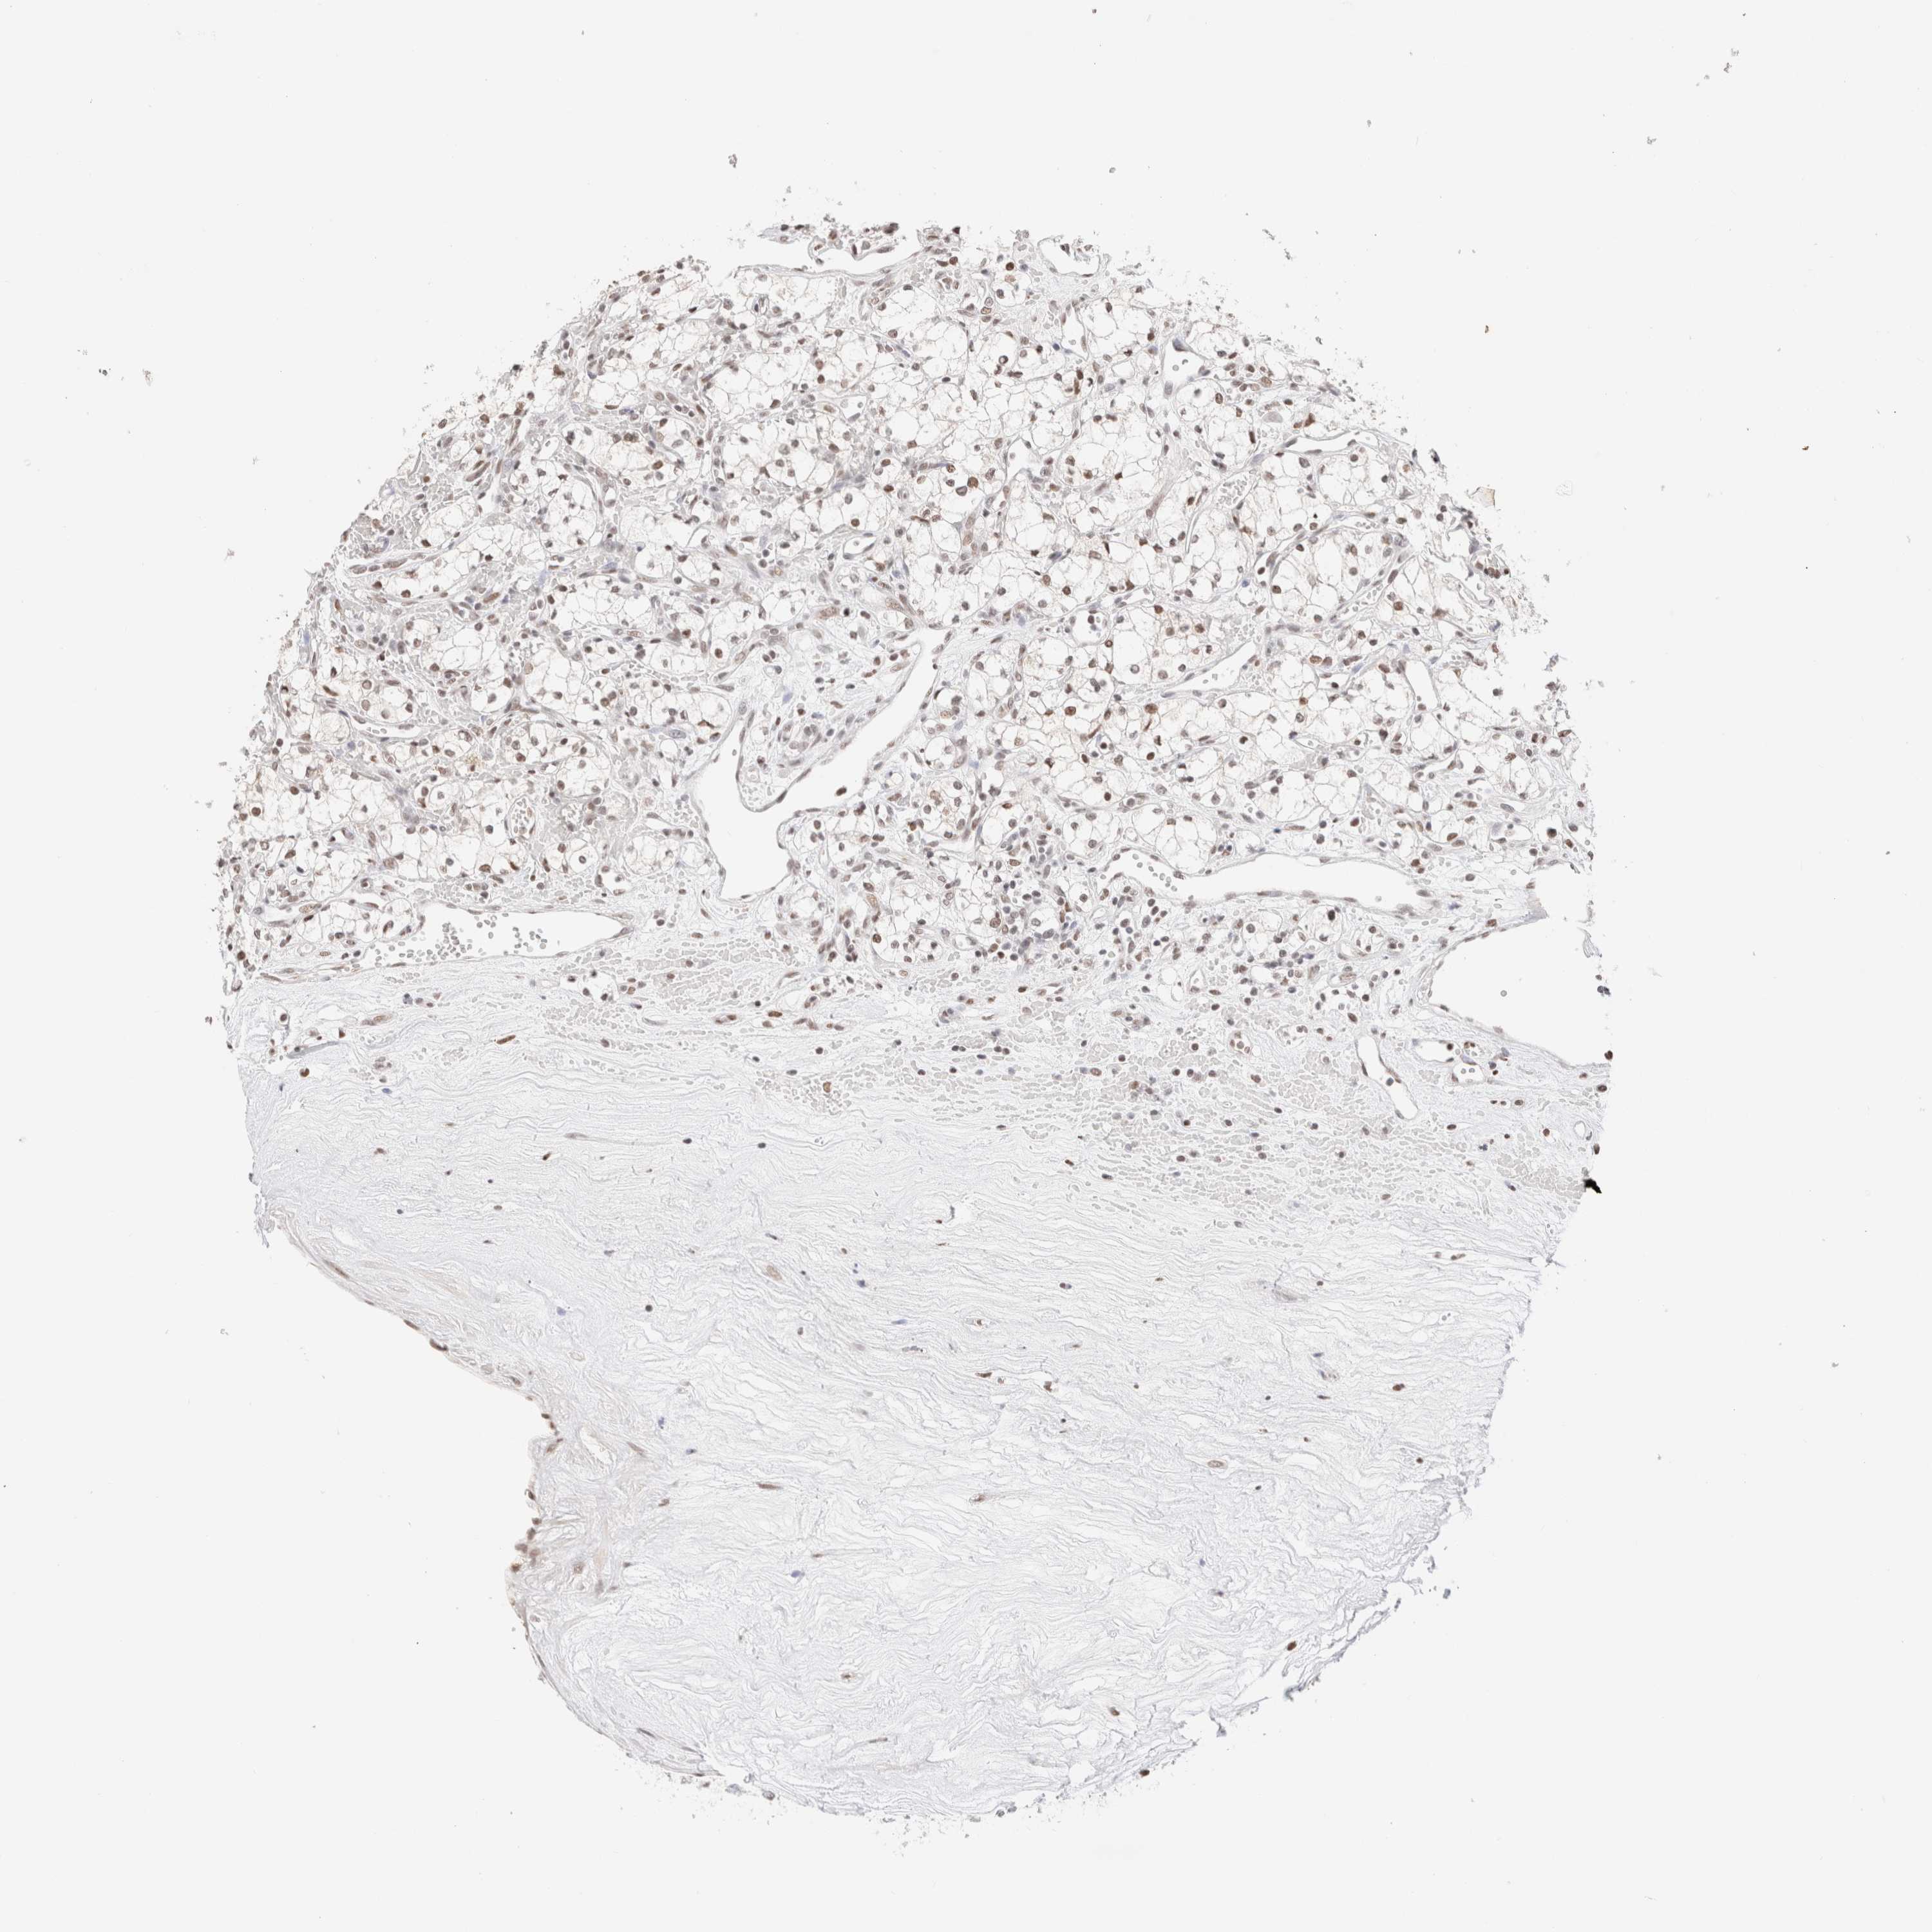

KIDNEY CHROMOPHOBE (TCGA) - Interactive survival scatter ploti

SUPT3H is not prognostic in Kidney Chromophobe (TCGA)

: 1.37

Average pTPM 3.4

Number of samples 64